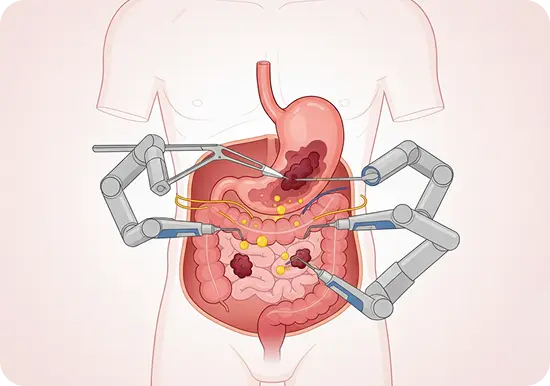

Gastrointestinal Oncology

- Surgery for stomach and colorectal cancers

- HIPEC (Hyperthermic Intraperitoneal Chemotherapy) for advanced GI cancers

- Minimally invasive and robotic-assisted pancreatic surgery

- Laparoscopic and robotic-assisted gastrointestinal surgeries